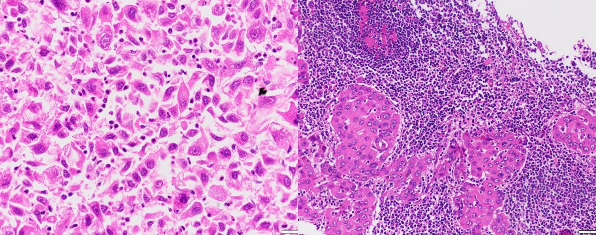

Ảnh 3.2. UTBMTBG đa hình thái, không biệt hóa (A) (HE x 200, mã số: 4257-18), UTBMTBG típ giàu lympho bào (B) (HE x 200 mã số: A87578)